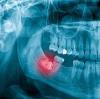

Зуб мудрости под десной, частично вышел.. Кто удалял такой: Долго ли длится удаление?

ну это снимок надо делать, смотреть в какую сторону растёт зуб, на сколько он глубоко, не видя ситуации невозможно сказать, один зуб мудрости который частично вышел у меня удалили за буквально 15 мин, а другой зуб который тоже торчал удаляли час, очень сложный оказался